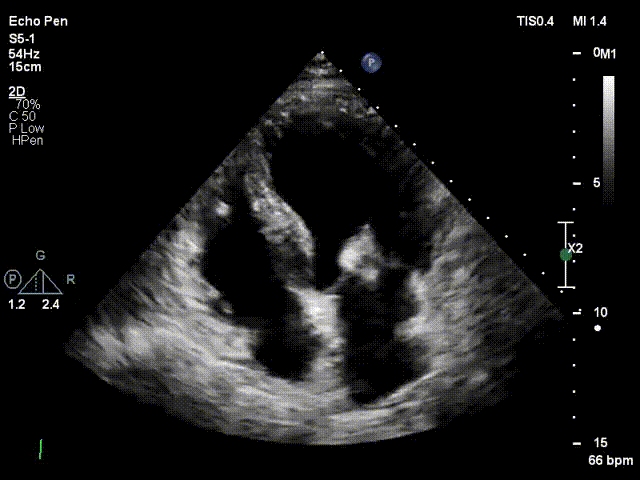

术后30天随访超声结果显示二尖瓣反流为轻度